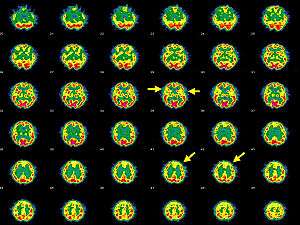

| Brain SPECT transaxial images of a patient afflicted with Hashimoto's encephalopathy. | |

- Single photon emission computed tomography shows focal and global hypoperfusion (75% cases)